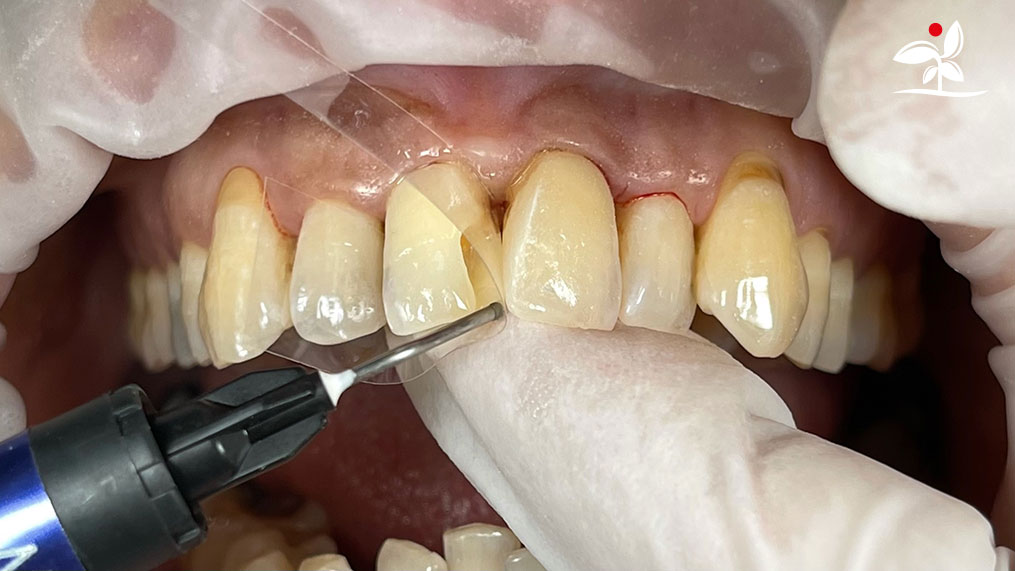

Restoration of Class IV Lesions using Naturomimetic Layering Technique (NLT) and Bioactive Restorative Materials

With the growing awareness about the health, function and aesthetic benefits of preserving natural tooth structure, patients are now globally demanding for aesthetic dentistry with minimally invasive procedures that has a low biological cost. This public demand has encouraged logical clinicians to adopt to the minimally invasive cosmetic dentistry (MiCD) concept and its treatment protocol [1] in their practice. The author has been using MiCD concept and its treatment protocols since 2017, which

include the methods of treatment that are simple, fast, predictable and healthy. In aesthetic restoration, the tooth color restorative materials placement technique is one of the most challenging, confusing and frustrating areas to learn owing to the multiple techniques that have been proposed by many clinicians and replicating such techniques in practice is not always as easy as they are marketed in dentistry. Natural teeth are complex in structure and hard to simulate due distribution of colors through enamel and dentin [2]. Aesthetic restoration strategies should follow proper understanding of defects, right selection of restorative materials along with their proper application, finishing, texturing and polishing [2].